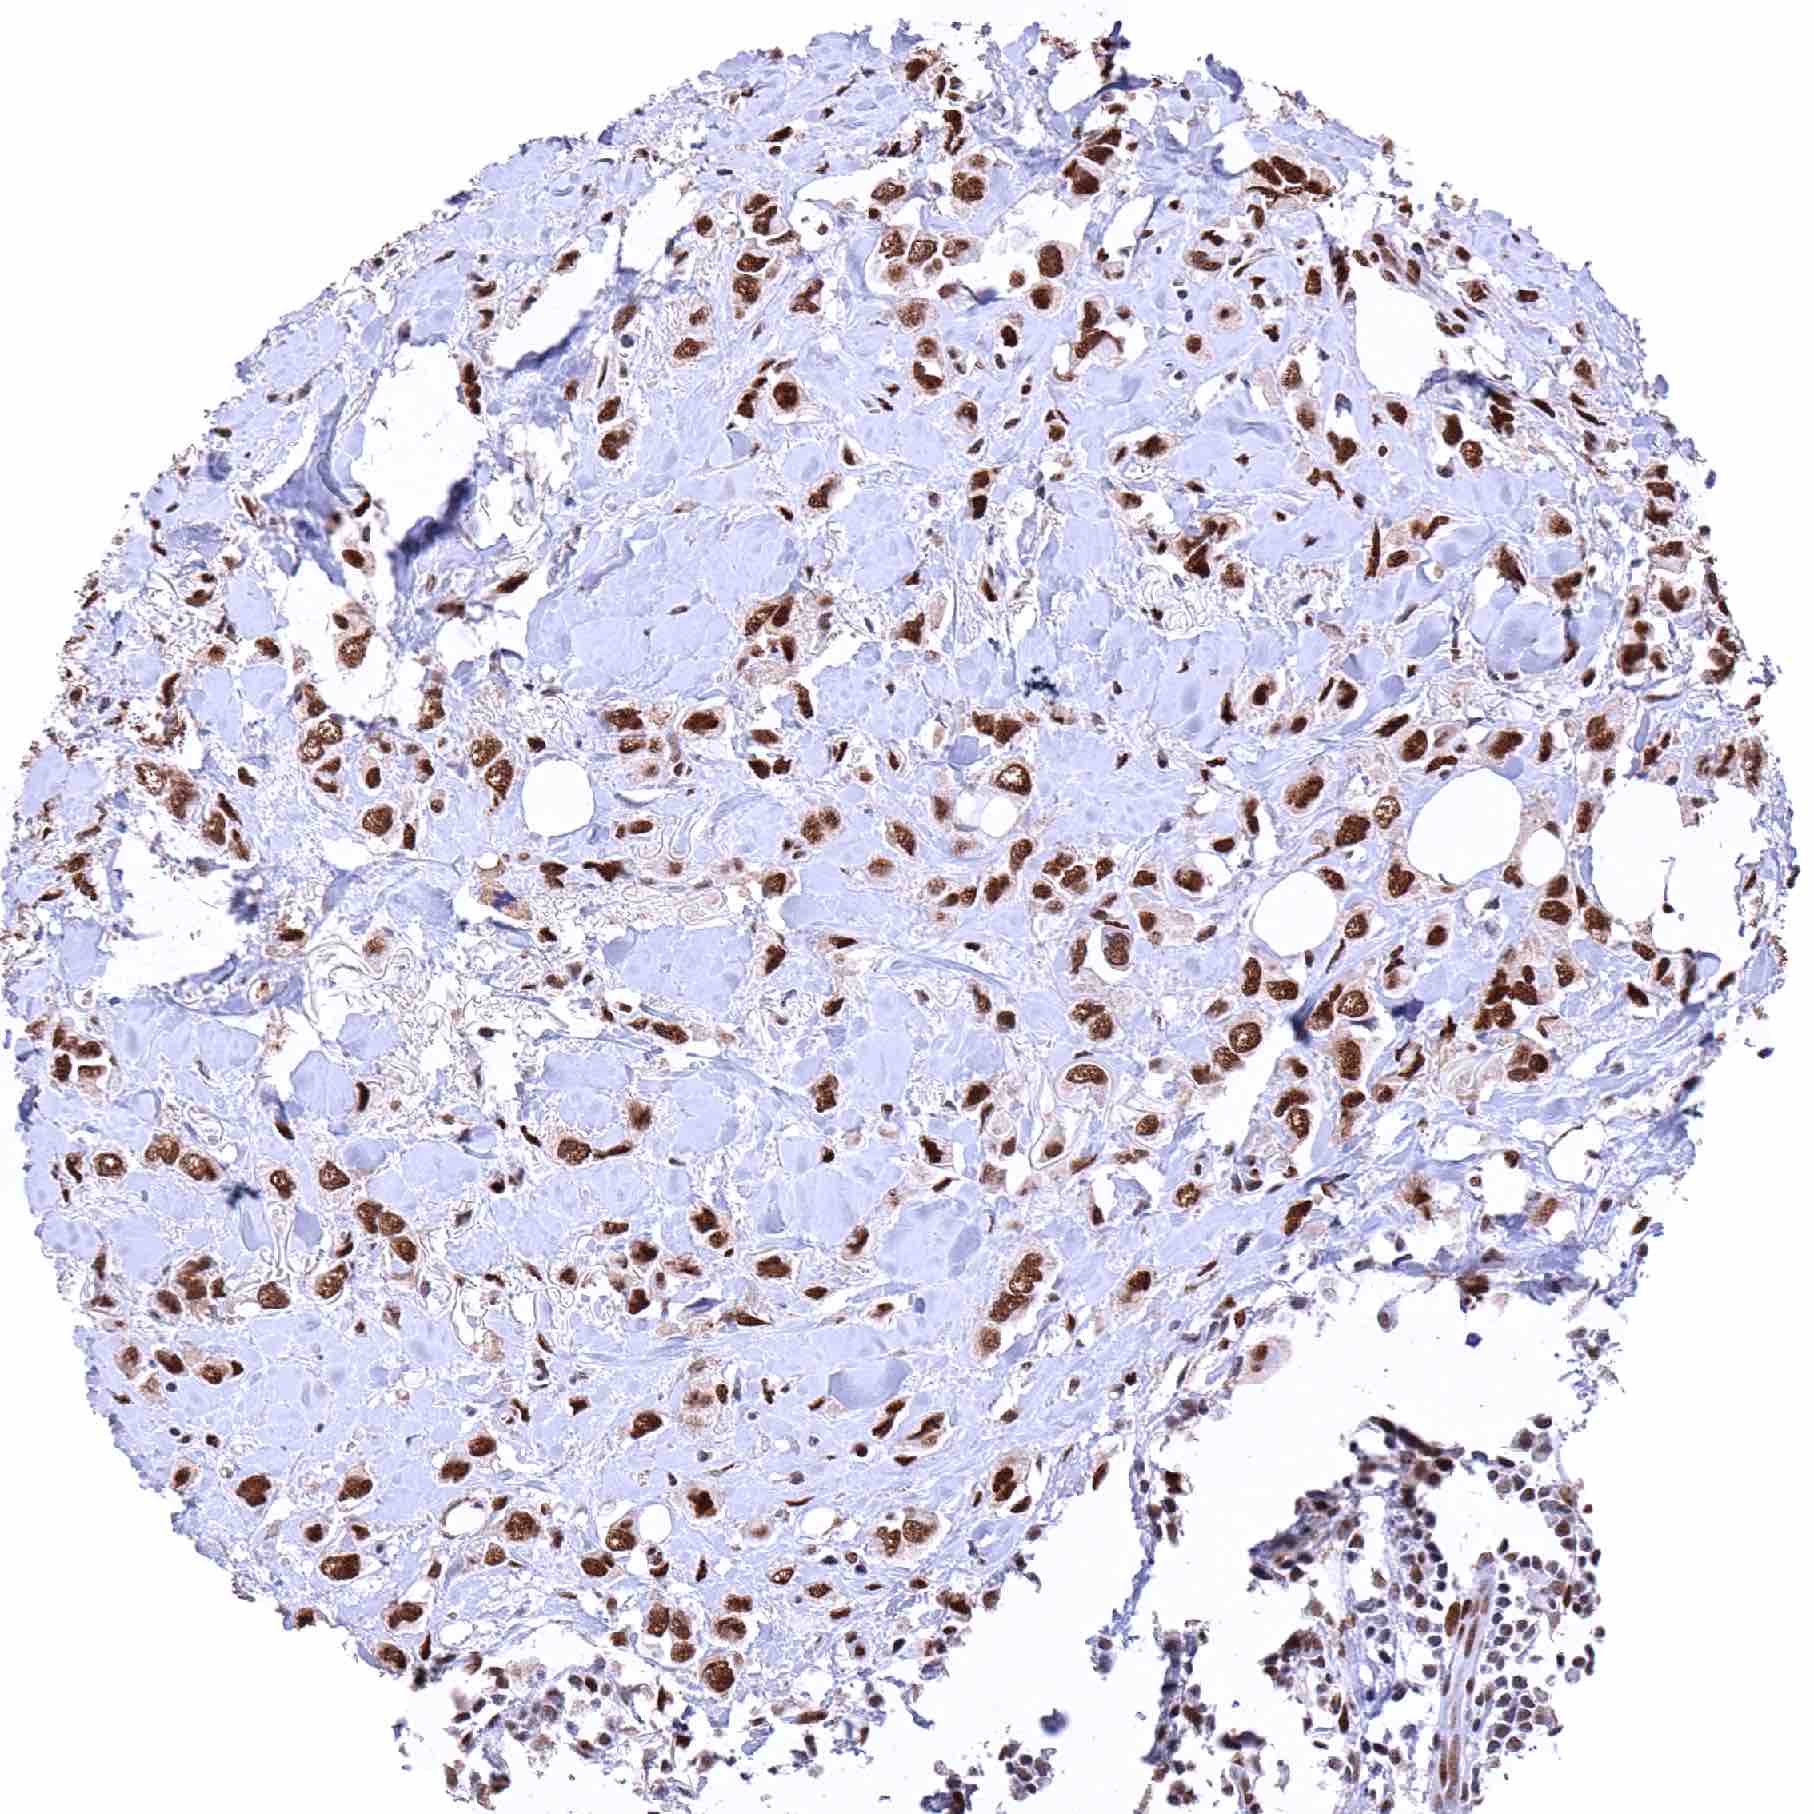

Kidney – Clear cell renal cell carcinoma with distinct 53BP1 positivity of tumor cells